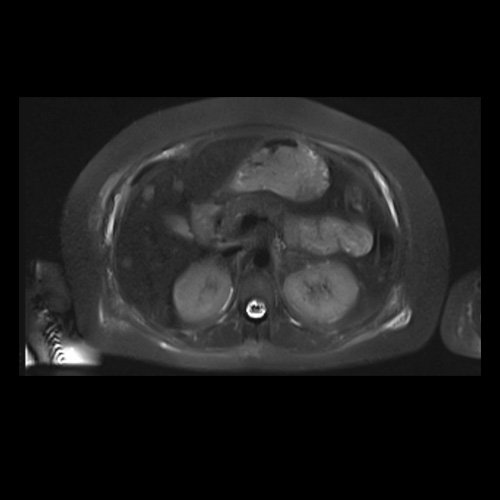

RMI abdomen y pelvis con contraste EV (14/02/26): En las bases pulmonares se visualizan atelectasias laminares bibalsales. No se identifica derrame pleural. El hígado es de forma, tamaño y situación normal. La superficie es lisa, los bordes son agudos. Se observan múltiples lesiones sólidas de distribución difusa, levemente hiperintensas en T2, con restricción en difusión y realce homogéneo tras la administración de contraste EV, la de mayor tamaño de 15 mm en segmento VII. Sugiero conocimiento histológico. La vía biliar intra y extrahepática es de calibre conservado. La vesícula biliar es de forma y situación habitual, sus paredes son finas y no presenta imágenes hipointensas en su interior, que sugieran la presencia de litiasis. El bazo es de forma, tamaño y situación normal, sin efectos de masa focales. El páncreas es de forma, tamaño y situación normal, sin efectos de masa. El Wirsung es de calibre conservado. Glándulas adrenales de forma, tamaño y situación normal, sin efectos de masa. Ambos riñones son de forma, tamaño y situación normal, con adecuada diferenciación córtico subcortical. No se observan alteraciones a nivel de la vía excretora. No se observan adenomegalias retroperitoneales ni intraperitoneales. La aorta abdominal, las arterias iliacas primițivas, internas, externas y femorales son de trayecto y calibre normal La vena cava inferior, las venas ilíacas primitivas, internas, externas y femorales son de trayecto y calibre normal. No impresionan alteraciones a nivel del tracto gastrointestinal. La vejiga es de paredes finas, normalmente distensibles, sin evidencia de lesiones endoluminales ni parietales. Mioma transmural en hoja anterior de útero que mide 55 x 47 mm sin signos de complicaciones. Imagen ovalada de contenido líquido que mide 65 x 52 mm en el espesor del tejido celular subcutáneo de región antero-superior de muslo derecho, por delante de músculo sartorio, que no presenta realce tras la administración de contraste EV.

RMN de abdomen con contraste endovenoso (14/02/26) Corte axial (T2): múltiples lesiones sólidas de distribución difusa, levemente hiperintensas.

RMN de abdomen con contraste endovenoso (14/02/26) Corte coronal (T2): adenoma suprarrenal izquierdo; lesión hepática redondeada hiperintensa redondeada en segmento VII.